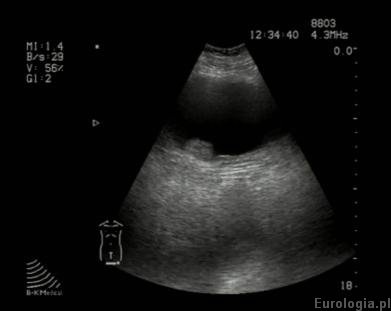

Badanie USG pozwala na rozpoznanie większości guzów pęcherza o wielkości powyżej 10 mm. Nieprawidłowy obraz USG - podejrzenie guza pęcherza upoważnia lekarza do takiego rozpoznania. W zależności od oceny ultrasonograficznej urologa pacjent może być zakwalifikowany do cystoskopii - wziernikowania pęcherza moczowego lub TURT - przezcewkowej resekcji guza jeśli obraz USG ewidentnie budzi podejrzenie choroby nowotworowej.

Fot. Guz okolicy ujścia prawego moczowodu - obraz USG.